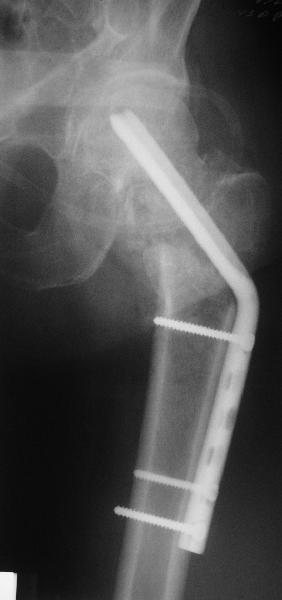

Приветствую всех. Спасибо за активное участие в обсуждении. Выбрали вариант с остеотомией.

Снимки в приложении.

Надеемся на днях поднять на костыли.